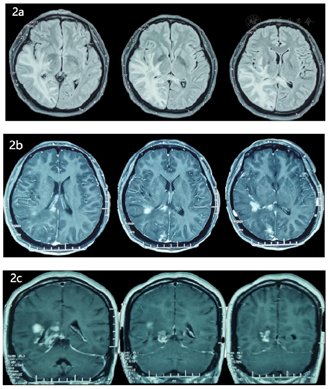

辅助检查:脑脊液压力230mmH20,蛋白0.52g/L,余常规、生化、细胞学未见异常。头颅磁共振成像(magnetic resonance imaging, MRI)增强示右侧颞枕叶、胼胝体多发结节样及短条状异常高信号(图2);磁共振波谱成像(magnetic resonance spectrum, MRS)提示所选右侧颞枕叶感兴趣区Cho峰升高,NAA峰降低,Cho/NAA约0.65-2.01;头弥散张量成像(Diffusion Tensor Imaging, DTI):右侧颞枕叶可见片状异常信号,FA值减低,其内神经纤维明显减少、部分断裂;颅内磁共振静脉血管造影(magnetic resonance venography, MRV)提示左侧横窦显示不清,右侧横窦-乙状交界区显影浅淡;颅内磁共血管造影(magnetic resonance angiography, MRA)未见明显异常。2021年04月30日于北京协和医院神经科门诊就诊,头颅MRI增强及弥散加权成像(diffusion-weighted imaging, DWI)显示右内囊后肢、侧脑室后角旁、顶枕叶异常信号,体积减小,散在结节状强化,DWI信号不高,考虑炎性疾病可能。多学科会诊意见:影像学提示:右侧颞枕、海马区多发散在病变,目前证据尚不能明确病变性质,结合患者有硬皮病病史,不除外硬皮病累及中枢神经系统改变,建议活检。

文献报道的影像学表现有皮肤同侧的同侧局部脑萎缩、白质脱髓鞘、脑实质钙化等[8]。绝大多数的患者头颅MRI会出现不止一个部位的T2高信号,最常见的部位为皮层下脑白质、其他还包括胼胝体、深部灰质核团、脑干等[8,9]。值得注意的是,头颅增强MRI有异常信号的部分患者,尽管经过几年的免疫抑制治疗,强化信号仍然存在甚至增强[7]。这提示此类患者的中枢神经系统内仍有活跃的炎性反应。本例患者为右侧额面部局限性硬化症,同时影像学病灶也位于右侧,符合典型的局限性硬化症相关中枢神经系统血管炎表现。患者在应用半年免疫抑制治疗后复查头颅增强MRI,病灶仍有强化但体积缩小,提示免疫抑制治疗有效。